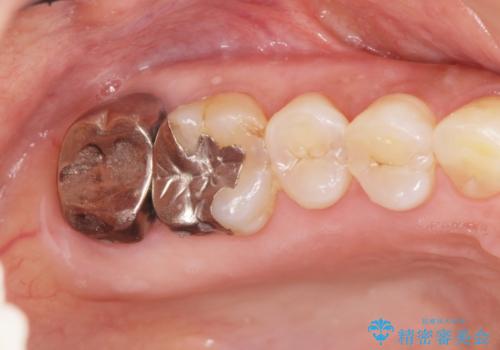

歯髄方向 歯肉方向へと深い 2種類の大きな虫歯

#17は失活歯で歯肉方向への縁下カリエス、#16は生活歯であるものの歯髄ギリギリの処置となるであろうとが予想される治療です。